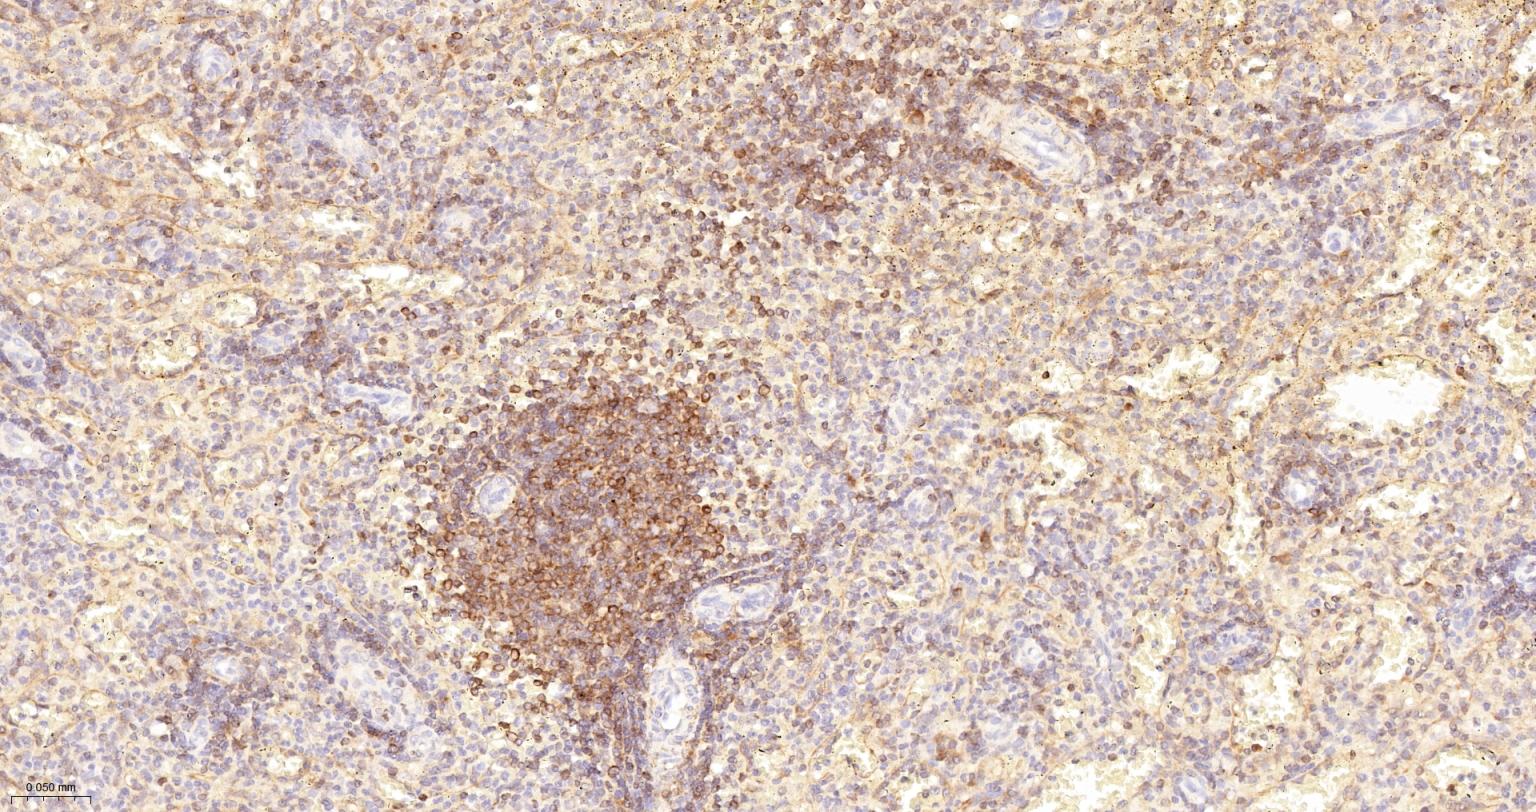

| IHC-P | Human, Mouse | 1:100-500 | |

Cancer > Cell Death > Apoptosis > Apoptosis Markers > Bcl 2 family

Cell Biology > Apoptosis > Intracellular > Bcl2 Family